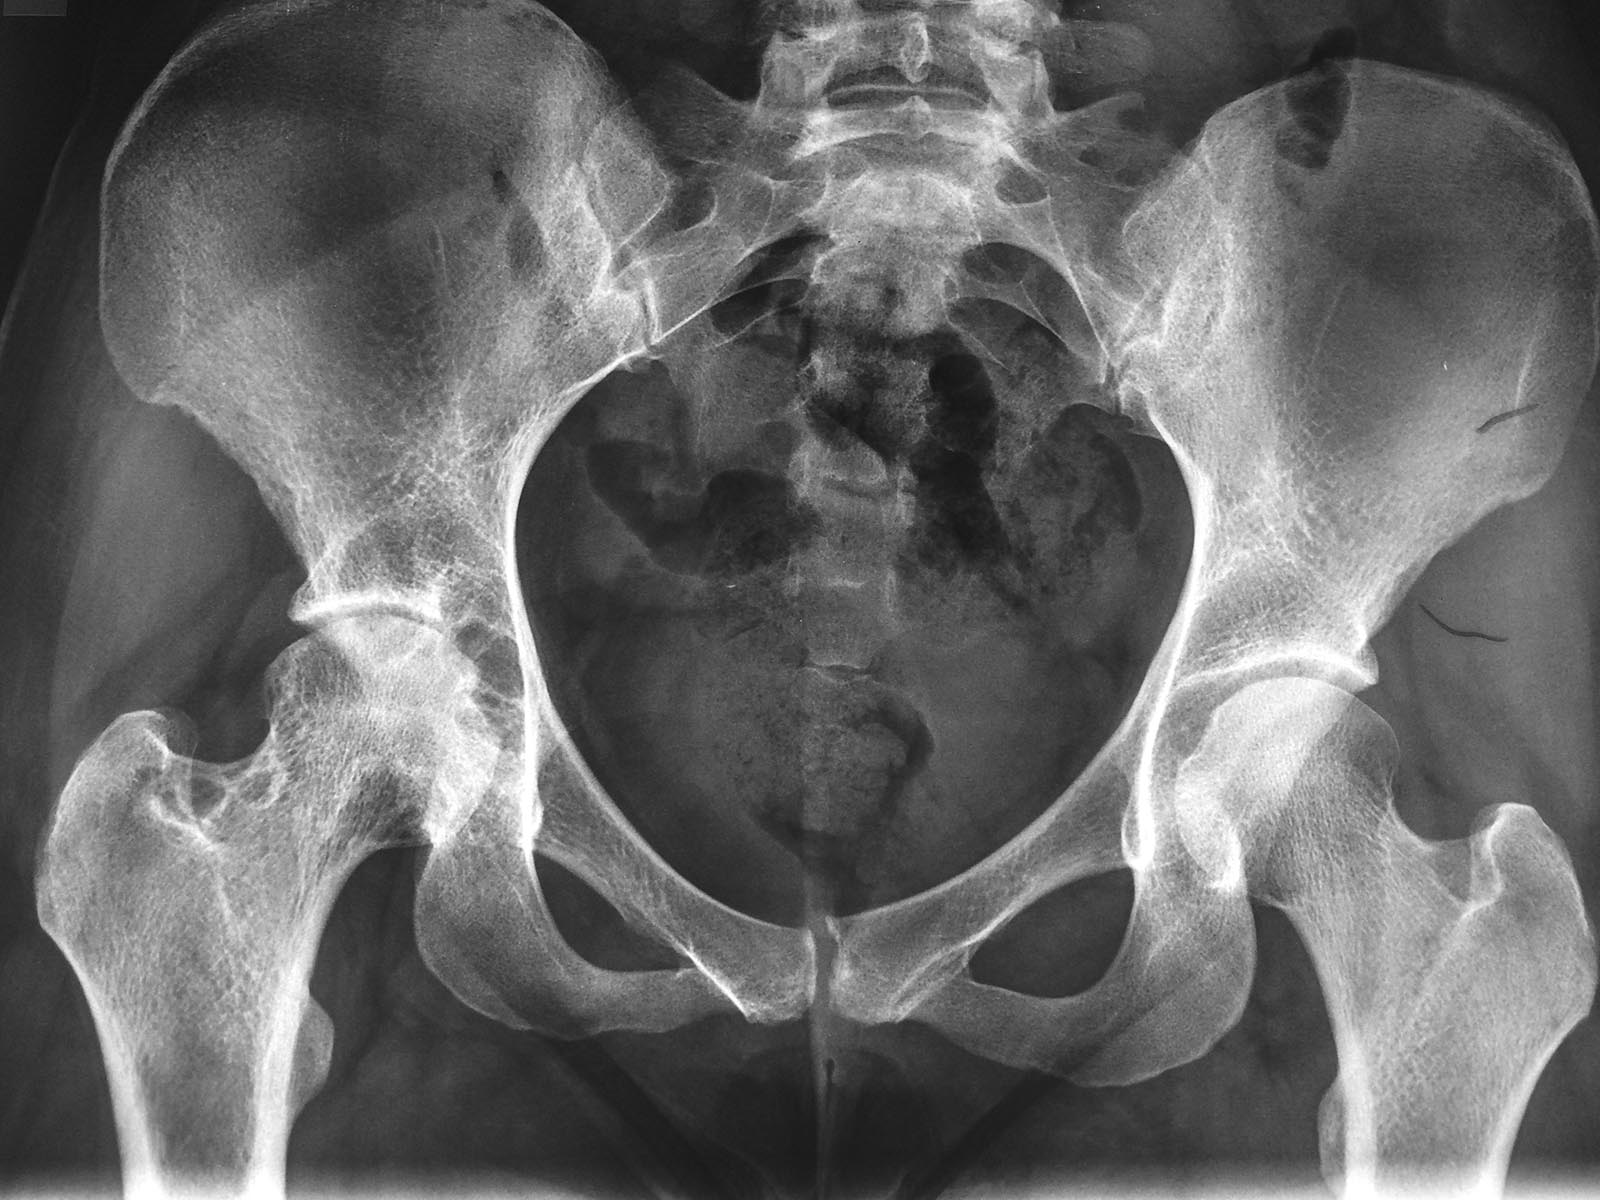

[Ortho] ПВУС тазобедренного сустава

Снимок.